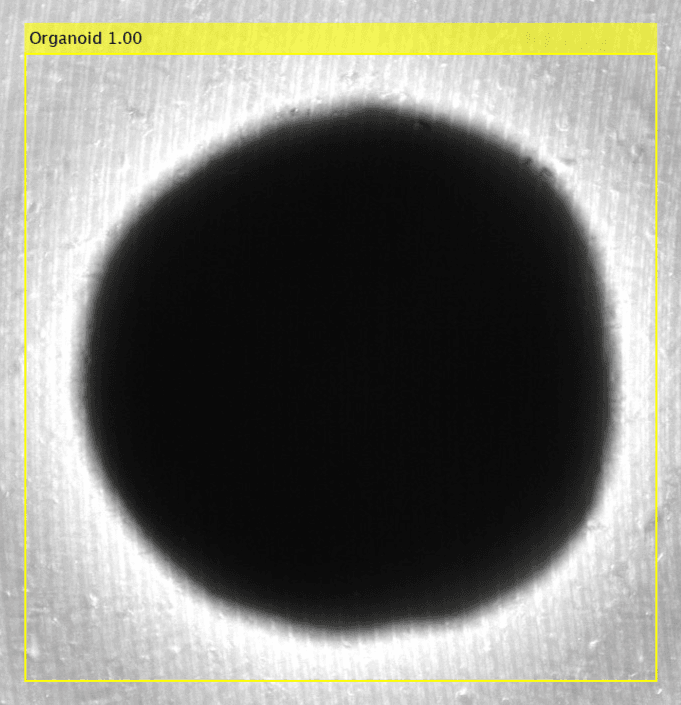

Organoids